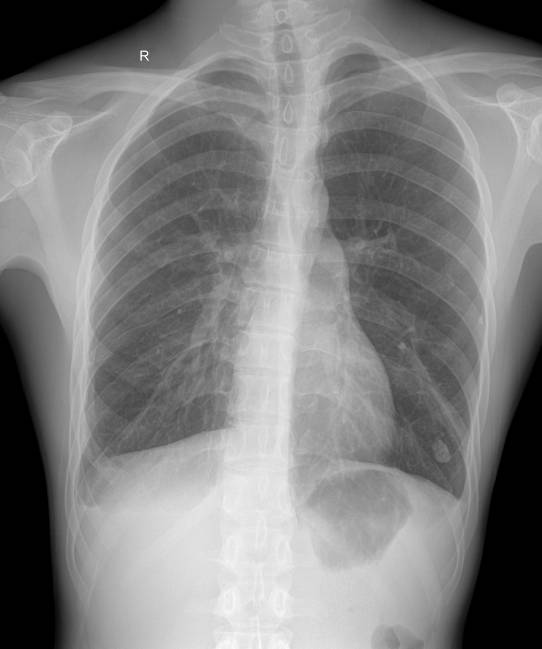

呼吸系统:

既可胸部DR也可在透视下直接胸部数字点片;